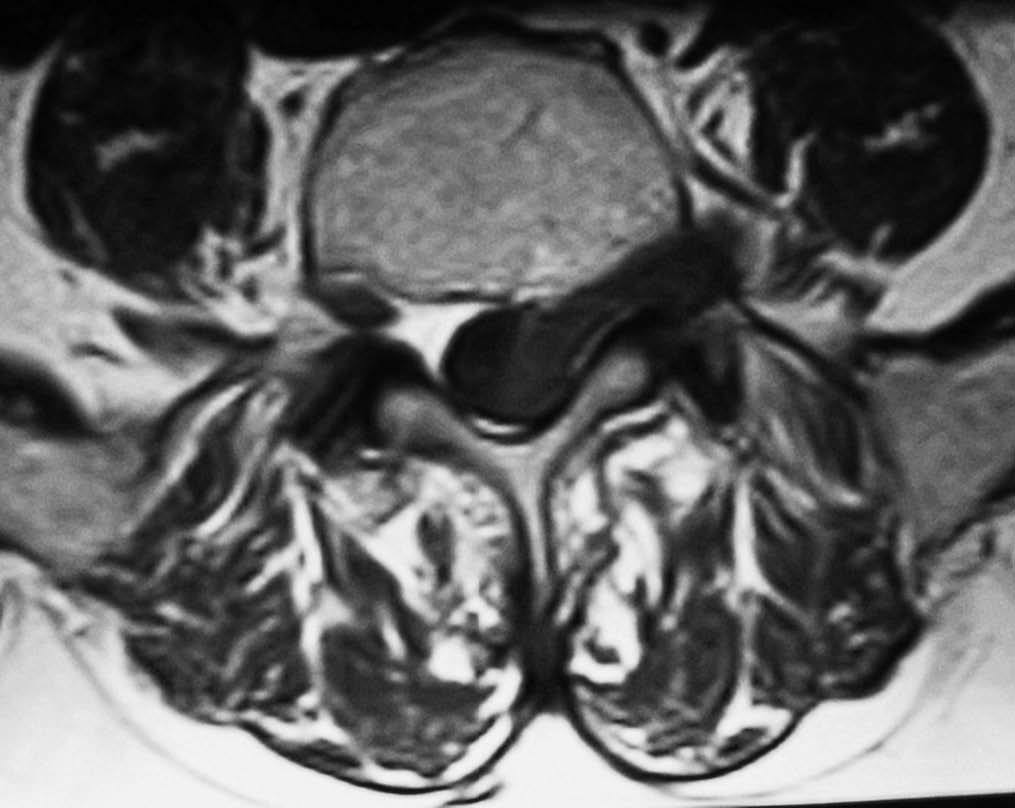

Fig. 3.--RM secuencia SE pT1. Corte axial. Lesión en canal, foramina y espacio extraforaminal isointensa con respecto al músculo.